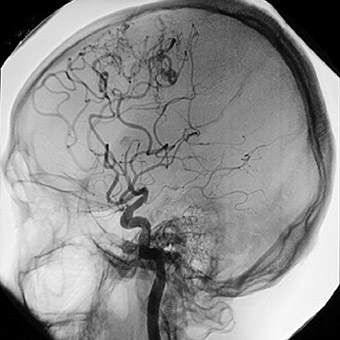

Elektriksel aktivitenin eksikliği beyin ölümünün teşhisini destekler. Beynin kan akışına bakan testler de yapılabilir.